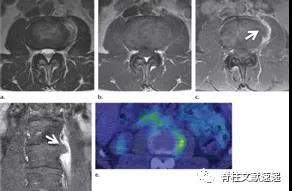

图注:49岁男性,极外侧腰椎间盘突出症。

图注:49岁男性,极外侧腰椎间盘突出症,有黑色素瘤病史。(e) 轴位PET图像显示病灶部位有FDG摄取,怀疑黑色素瘤转移。经过3周的保守治疗,病人的病情有所好转。临床上并没有黑色素瘤诊断。